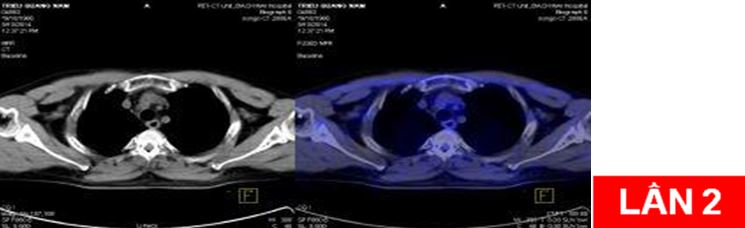

Bệnh nhân:chụp PET/CT lần 2 đánh giá sau 6 chu kỳ hóa chất (có đối chiếu với lần chụp trước khi điều trị).

Sau điều trị: không thấy nốt mờ và hạch di căn trung thất

Sau điều trị: hết u và hạch di căn